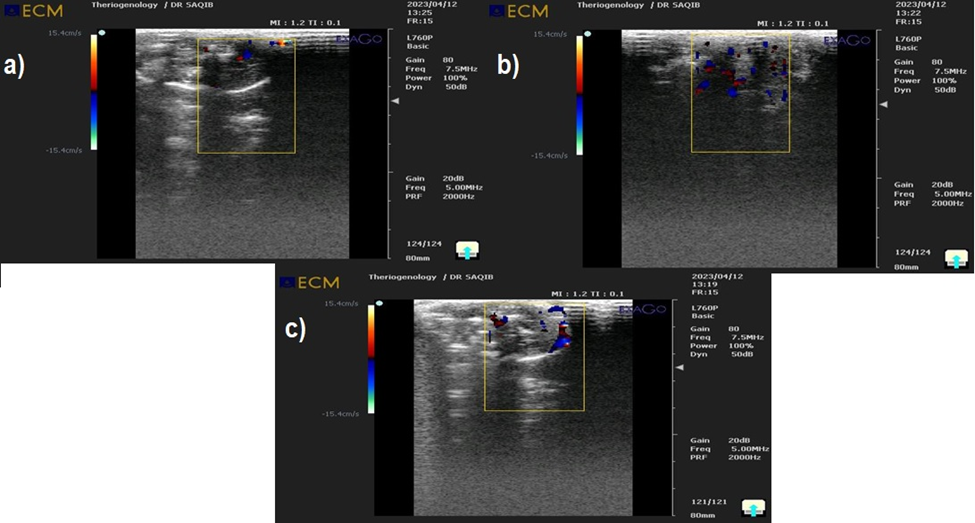

Animal trials

Numerous studies have been conducted to develop a strategy for thrombus induction in animal models [37], evaluated the in vivo activity of streptokinase on a rabbit model, so a rabbit was prepared for an in vivo investigation. For instance, Ferric chloride ions were employed to mimic the blood clot [38] created in the carotid artery of rats by inducing blood clots in the jugular veins of rabbits. In this study, thrombus was induced in the jugular vein using 20% FeCl₃ solution. Transamin was also used to create a thrombus in a rabbit’s carotids artery. One hour after the medicine was administered, the rate of thrombolysis was assessed. Determining thrombolysis in vivo is challenging since direct monitoring of plaque and thrombus is constrained.

Using ultrasonography, the specific location of thrombus formation in the rabbit model was found. This work used ultrasonography to identify the precise location of the thrombus and establish a link between the thickness of the aortic stenosis and thrombus formation, as described in [Fig. 2] (a), (b), and (c). Our results demonstrate that the blood clot-induced disintegration was brought on by the streptokinase injection. When compared with the samples of Immobilized streptokinase by Fe3O4 magnetic nanoparticles and native streptokinase with heparin control, the results showed that immobilized streptokinase (streptococcus pyogenes EBL-48) by Fe3O4 magnetic nanoparticles completely lysed the induced clot while native streptokinase without streptokinase partially lysed the induced clot. According to these findings, the infusion of 4000 IU of streptokinase caused the extensive systemic activation of the fibrinolytic system.

Figure 2:  Clot lysis using Native Streptokinase a): Ultrasound images of Induced Clot lysis By Native Streptokinase b): Immobilized by Fe3O4 magnetic nanoparticles c): Ultrasound images of Induced Clot lysis by Heparin as Control